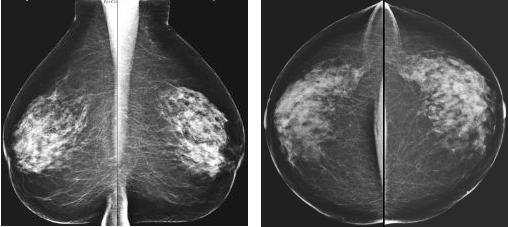

Exemple de cliché mammographique bilatéral (incidence

oblique)

1= glande mammaire 2= graisse sous-cutanée 3= muscle

pectoral